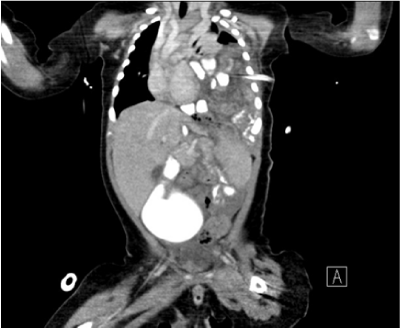

The hematologic and biochemical investigations were unremarkable except for leukocytosis (18, 800cells/μL). Clear yellowish fluid was drained from chest tube and the pleural fluid turned to milky white on the next day. Pleural fluid analysis revealed pH 7.5, LDH 116U/L, protein 20.9g/L, glucose 362mg/dL, total cholesterol 8 mg/dL, triglyceride 391mg/dL, and predominance of lymphocytes, which of them were all compatible with chylous effusion. A computed tomography of the chest and abdomen showed left pleural effusion, lung atelectasis and retention of bowel loops in the anterior aspect of left hemi-thorax (Figure 2). The finding was consistent with diaphragmatic hernia.

Figure 2 Chest CT demonstrated left diaphragmatic hernia and bowel loops, which contained barium contrast, in left thorax with pleural effusion and lung atelectasis.